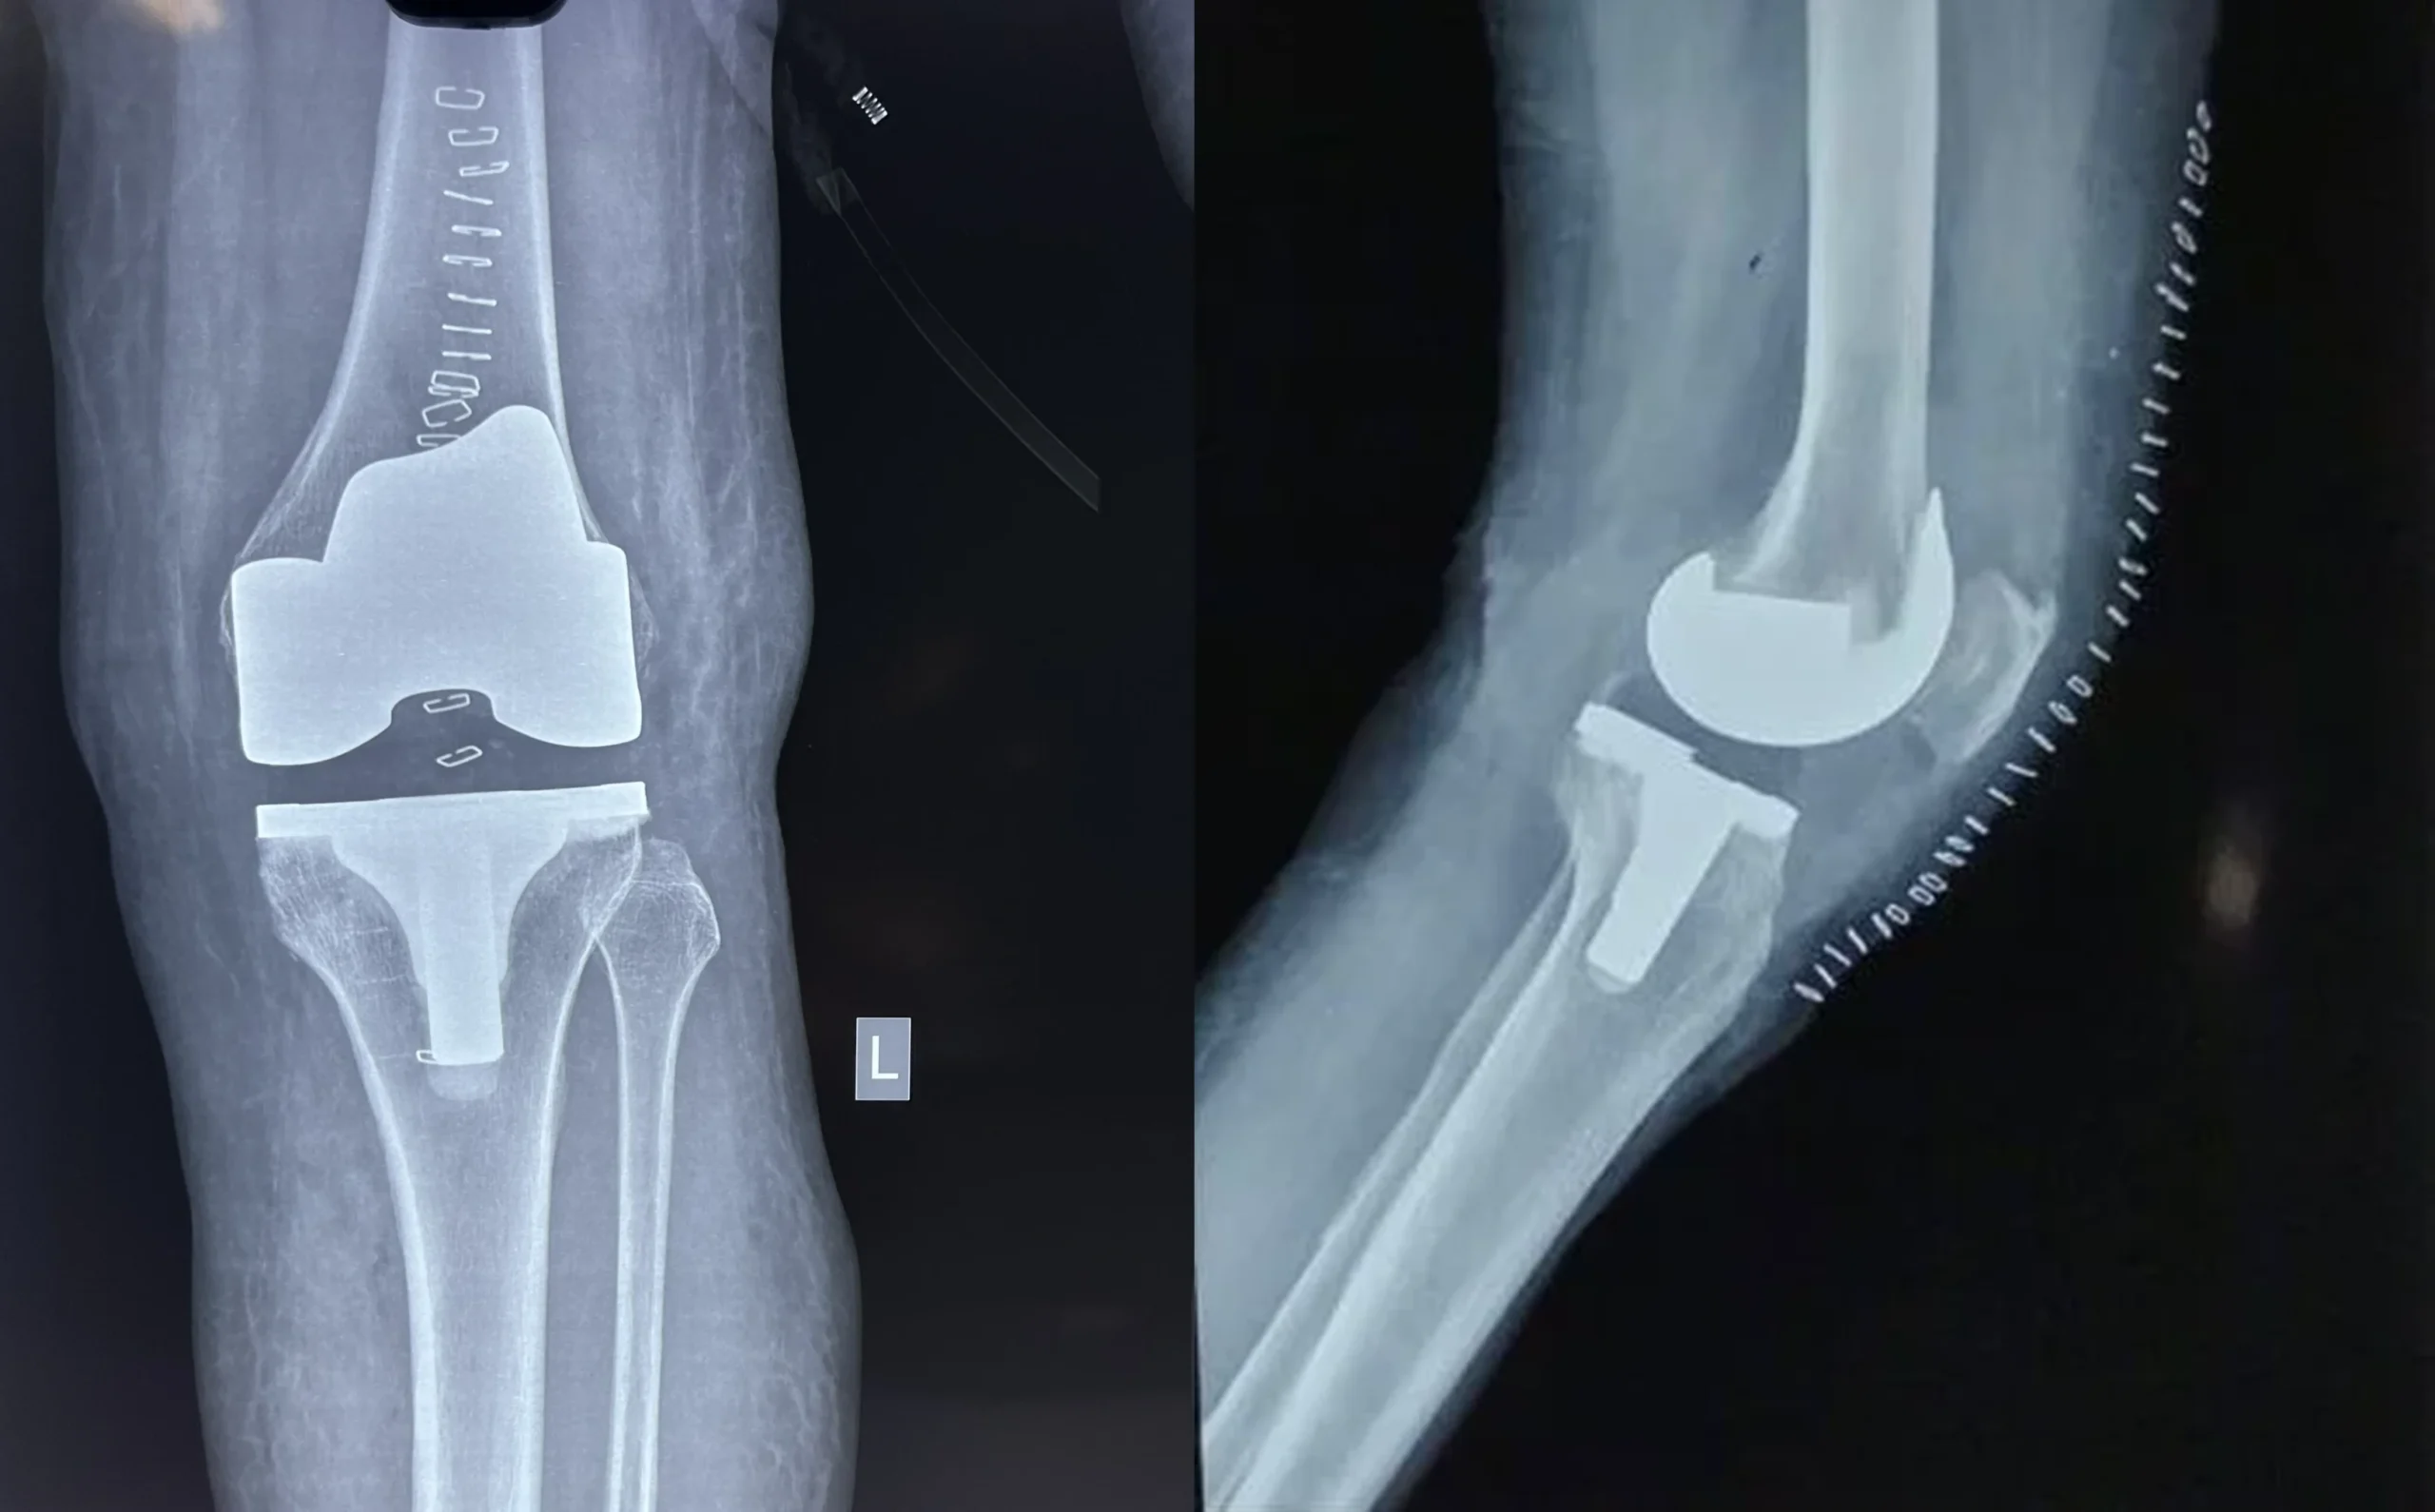

Synovitis with Loose Body in Rheumatoid Arthritis

Pre-Op X-Ray

Post-Op X-Ray